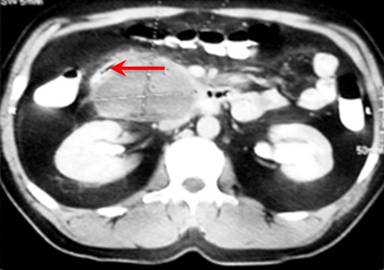

An abdominal computed tomography (CT) scan illustrated a 9x8 cm, solid, septated, cystic mass in the head of the pancreas (Figure 1). The mass had not invaded any adjacent organs. There was no evidence of lymphadenopathy on the CT scan. Furthermore, the level of the CA 19-9 tumor marker was within the normal range which made the diagnosis of malignancy less likely.

|

Figure 1. Abdominal CT scan. A large cystic lesion was located in the head of pancreas and had displaced the duodenum laterally (arrow). (Courtesy of Dr. Moradi). |